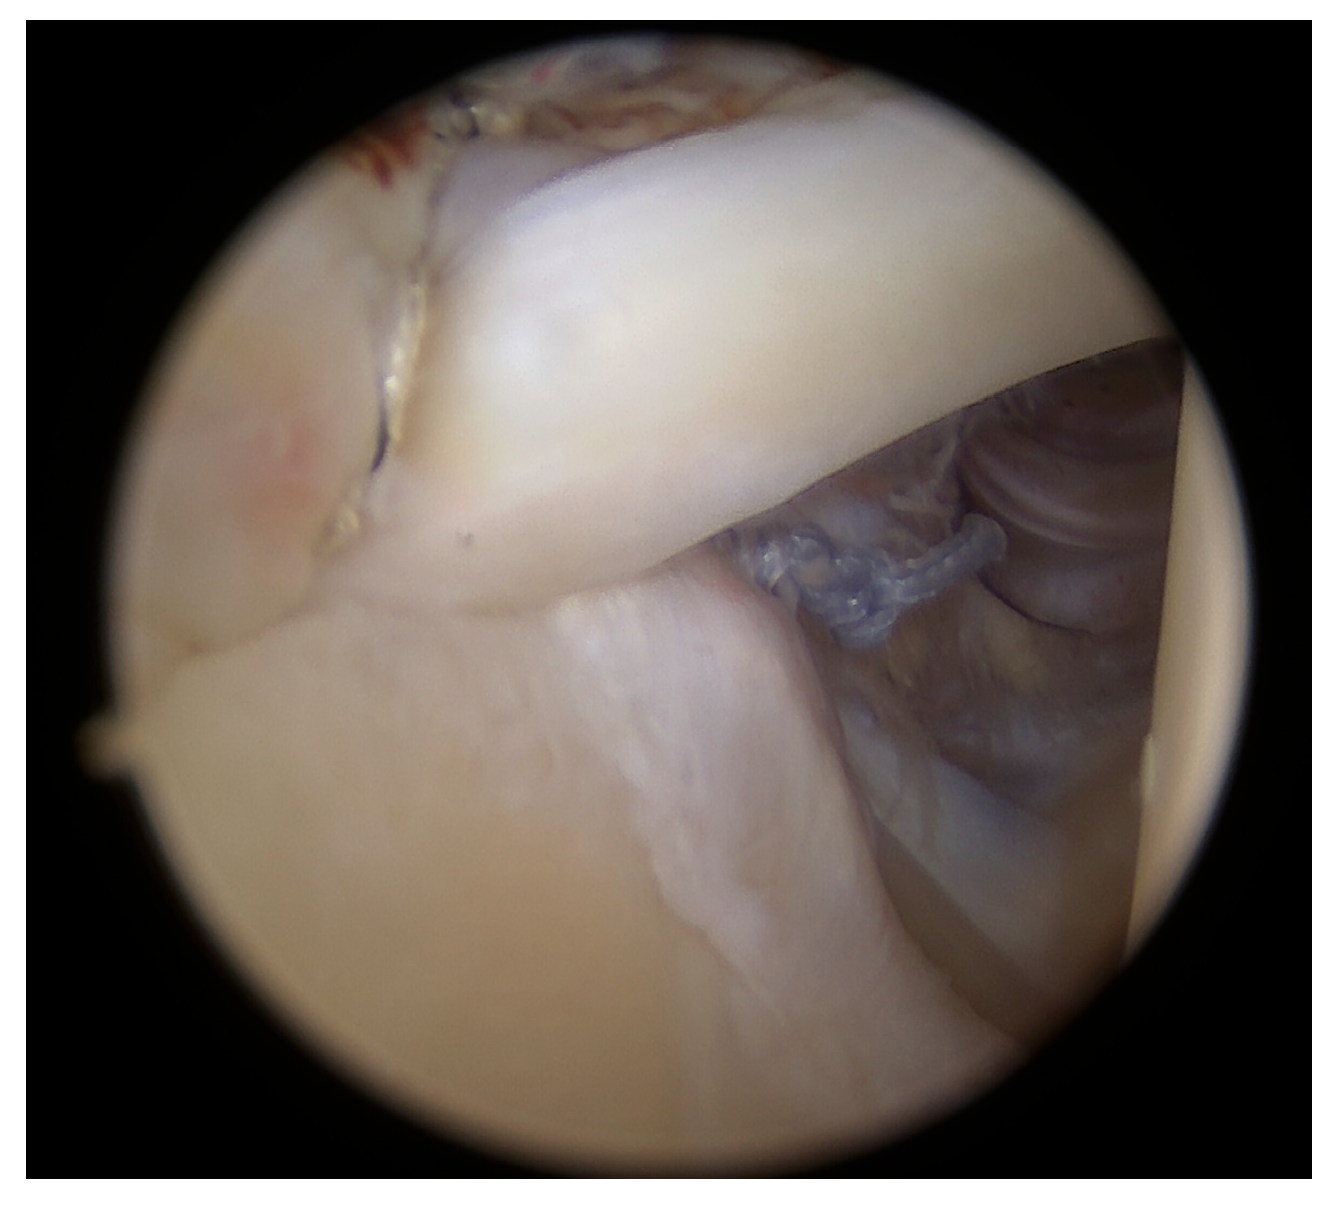

During the surgery, approximately at the time when enough bursal tissue had been collected, 15 mL of venous peripheral whole blood was drawn from one of two major veins from the contralateral arm, the median cubital or antebrachial part of the cephalic vein, using a 1 Arthrex ACP double syringe (Arthrex ACP, Munich, Germany). The blood was processed using a Hettich centrifuge at 1500 rpm for 5 min, obtaining 4–7 mL of autologous conditioned plasma (Arthrex ACP, Munich, Germany), which was then mixed by a scrub nurse with the harvested bursal tissue in a 1:0.3 ratio (bursal tissue:ACP) using 2 syringes connected through a female-to-female adapter. By pushing back and forth several times, a uniform pasty mass was created, and a 1 mL syringe was connected to the application cannula. Then, the fragments were transferred into the applied cannula and were carefully pushed up to the cannula tip using a trocar until they appeared at the opening. Meanwhile, the supraspinatus and infraspinatus footprints were prepared by removing fibrotic tissue and debriding down to the cortical bleeding bone to optimize healing conditions. A double-row repair technique was used, with the first row anchored near the cartilage border using titanium CorkScrew anchors (Arthrex, Munich, Germany), followed by the fixation of a suture bridge with BioPushLock anchors (Arthrex, Munich, Germany) (Figure 3a,b).

Figure 3.

Double-row repair using titanium anchors (a) and a suture bridge fixation (b).